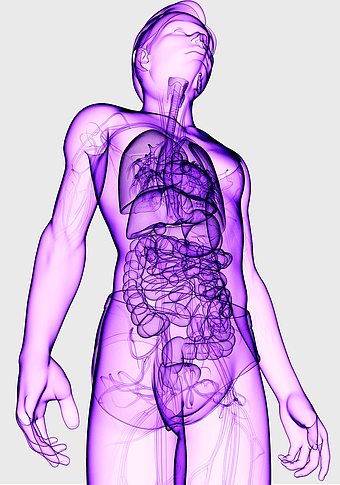

human anatomy illustration, purple medical figure, human body healing art, quantum health visualization, anatomical organ depiction, therapeutic body diagram, violet human structure -